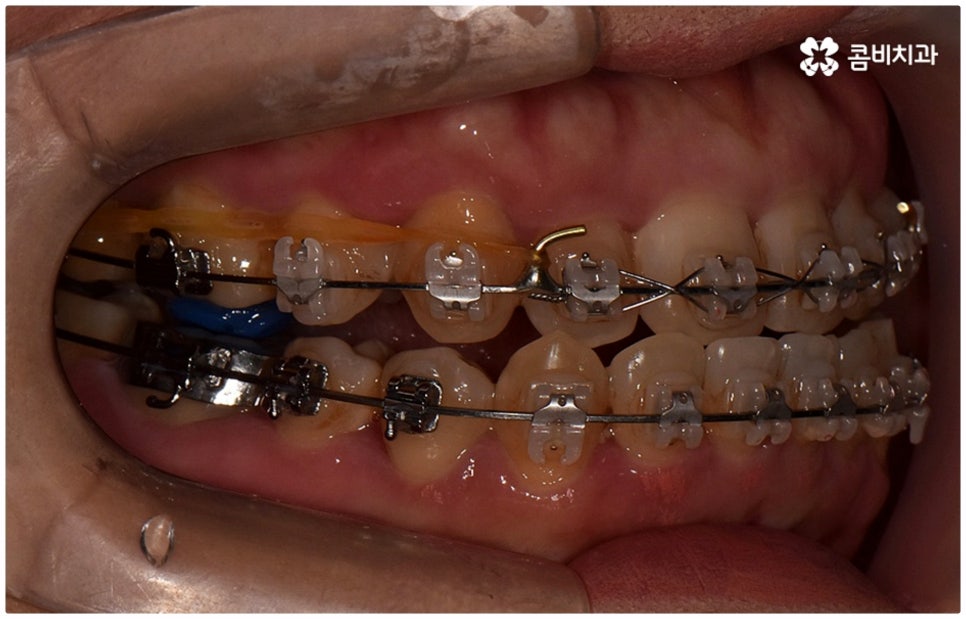

출처 아카이브 열기위아래 치열이 제대로 맞물리지 않으면 음식물을 씹을 때 어려움을 느끼거나 발음상 문제가 생길 수 있습니다. 이것을 부정교합이라고 하며, 그 종류는 상악과 하악의 골격적인 전후방 관계를 기준으로 1급, 2급, 3급으로 나눌 수 있어요. 위아래 어금니는 잘 맞물리는데 치열이 조금씩 삐뚤어져 있거나 치아 사이가 벌어져 있는 등 살짝씩 어긋난 부정교합은 1급, 위 어금니가 더 앞으로 나가있는 부정교합은 2급 (ex. 돌출입), 그리고 아래 어금니가 더 앞으로 나가있는 부정교합은 3급 (ex. 주걱턱) 으로 분류하게 되는데 이 중 오늘 살펴보려고 하는 것은 부정교합 3급에 해당하는 반대교합에 대한 거예요.

정상적인 교합은 윗 앞니가 아래 앞니를 살짝 덮는 정도로 윗니가 조금 더 앞으로 나와 있으면서 위아래 치아가 어금니까지 잘 맞물리는 것을 말하는데 반대교합은 위아래 앞니가 거꾸로 물리는 증상을 보이기 때문에 저작 활동 및 발음 조성이 원활하지 않게 되며 반대교합교정 등 적절한 치료를 받지 않고 방치할 경우 점점 더 주걱턱이 강화되는 쪽으로 뼈가 성장할 수 있어 될 수 있는 대로 빠른 시일 내에 원인을 분명하게 알아보고 그에 맞는 치료를 받는 것이 중요하다고 할 수 있어요.

골격적인 원인이 아니라면 위턱과 아래턱의 위치나 크기에는 이상이 없는데 치아의 맹출 각도 및 방향의 문제로 인해 치아가 반대로 맞물리게 된 치성 반대교합에 해당하는 경우라고 할 수 있는데요. 그 원인으로는 선천적인 치열의 문제 (아래턱 앞니 치축이 앞으로 기울거나 위턱 앞니 치축이 뒤로 들어감), 유치가 너무 빨리 빠지고 영구치가 자리를 제대로 잡지 못해 생긴 문제, 후천적인 습관 (혀를 내밀거나 손톱을 깨무는 등 치열에 좋지 않은 영향을 주는 행위를 지속적으로 반복) 으로 인한 문제 등등을 살펴볼 수 있으며, 보통 이런 경우 앞니 4~6개 치아 일부에 국한된 문제이기 때문에 보다 빠르고 간단하게 교정 치료가 가능하므로 꼭 성장기에 치료를 시작하지 않고 성인이 된 후라고 해도 비교적 쉽게 개선이 될 수 있습니다.

반대교합의 경우 보통 두 원인이 혼재되어 나타나는 경우가 많으며 또한 환자분들의 상황에 따라 정확한 치료가 달라지기 때문에 꼼꼼한 검진 후 각자에 맞는 반대교합교정 치료를 통해 이를 바로잡아 주시길 권유드리고 있어요. 검진과 치료를 받을 때는 3D CT와 같은 정밀 검사 기계를 갖추고 있는 치과에서 임상 경험이 풍부하고 뛰어난 노하우와 기술을 가지고 있는 숙련된 의료진에게 반대교합교정 치료를 진행하는 것이 좋을 거예요.

교정 치료가 생물학적 반응을 이용하는 것이다 보니 성장기에 진행하면 치아 이동 및 회복 속도 등에 장점이 있는 것은 분명하지만 그렇다고 해서 성인 이후 중장년 분들이 교정 치료를 받을 수 없는 것은 아니며 이미 많은 분들이 도움을 받고 계신 만큼 이에 대해서 한 번 고려해 보시면 좋을 거예요. 혹시 성장기 이후로는 양악 수술 등으로만 치료가 가능한 것이 아닐까 생각하셔서 부담스럽게 느끼셨던 분들이라면 지레 겁을 먹고 불편함을 그대로 방치하시기 보다는 검진 및 상담을 통해 적극적으로 이를 해결해 보시길 권유드리고 있어요.

물론 원인과 정도에 따라 외과적인 방법이 필요하신 분들도 있을 수 있지만 교정을 통해 얼마든지 치료가 가능한 경우도 있으며 앞서 말씀드렸던 것처럼 발전된 교정 기술 및 특수 미니스크류 등의 장치 개발을 통해 턱의 방향을 조금씩 회전시켜 원거리 치아 이동을 유발하는 것이 가능해졌기 때문에 예전에는 한계가 있었던 부정교합 케이스도 개선될 여지가 늘어나고 있습니다. 꼼꼼하게 검진을 받으시고 자신의 상황에 맞는 교정 치료를 무리하지 않게 진행하신 후 철저하게 사후 관리를 해주시면 보다 오랜 기간 동안 건강하게 고른 치열을 유지하면서 생활하실 수 있을 거예요.